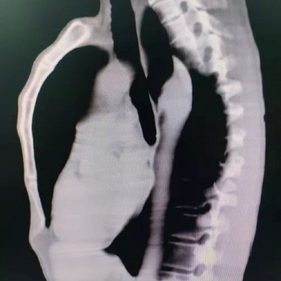

SURGERY FOR A 56-YEAR-OLD PATIENT WITH SEVERE PECTUS CARINATUM

The patient is a 56-year-old male who has had a protruding chest wall since childhood, with the deformity becoming more pronounced after puberty. Since he experienced no discomfort, he didn’t seek treatment. However, as he aged, he became increasingly dissatisfied with the appearance of his chest wall and felt immense psychological distress, leading him to seek surgical treatment.

The patient was diagnosed with severe pectus carinatum. Initially, the Wenlin procedure was performed to correct the protrusion. Two 4 cm incisions were made on each side of the chest wall, and three shaped bars were placed on the protruding bone structure. By pressing down on the protruding chest wall and continuously adjusting the curvature of the bars, the deformed chest wall was gradually restored to its normal contour. Lastly, the Wang technique was performed, which features a special bar fixation method that utilizes steel wires instead of short fixation bars to secure the ends of the shaping bars. This is the primary distinction between the Wenlin procedure and the Nuss procedure or the Abramson procedure. As a result, the bars were secured directly to the ribs on both sides of the chest wall.

Since the anterior chest wall is a rigid whole, manually pressing down the protrusion in the upper chest often causes a secondary depression below it. The Wung procedure was performed to correct this depression. To avoid damaging the heart when directly inserting the bar, a passage tunnel was carefully constructed by manual exploration, and the fourth bar was slowly placed into the chest cavity. The bar was used to elevate the depression, and its ends were secured using the Wang technique. After the surgery, the patient’s protruding deformity disappeared, and the chest wall appearance was restored to normal.